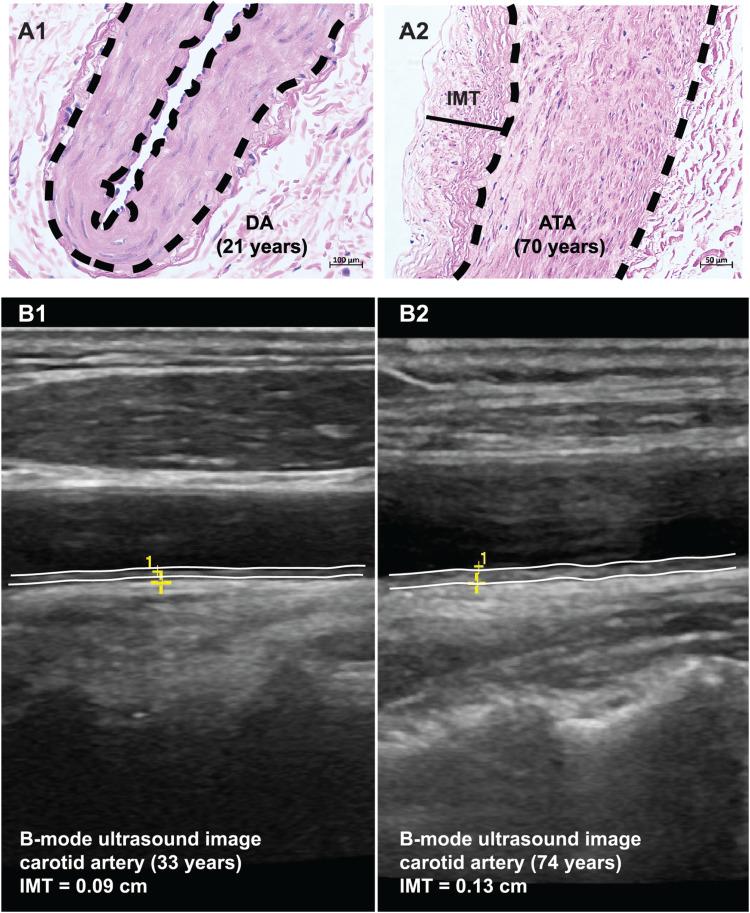

Vascular aging represents a collection of structural and functional changes in a blood vessel with advancing age, including increased stiffness, vascular wall remodeling, loss of angiogenic ability, and endothelium-dependent vasodilation dysfunction. These age-related alterations may occur earlier in those who are at risk for or have cardiovascular diseases, therefore, are defined as early or premature vascular aging. Vascular aging contributes independently to cardio-cerebral vascular diseases (CCVDs). Thus, early diagnosis and interventions targeting vascular aging are of paramount importance in the delay or prevention of CCVDs. Here, we review the direct assessment of vascular aging by examining parameters that reflect changes in structure, function, or their compliance with age including arterial wall thickness and lumen diameter, endothelium-dependent vasodilation, arterial stiffness as well as indirect assessment through pathological studies of biomarkers including endothelial progenitor cell, lymphocytic telomeres, advanced glycation end-products, and C-reactive protein. Further, we evaluate how different types of interventions including lifestyle mediation, such as caloric restriction and salt intake, and treatments for hypertension, diabetes, and hyperlipidemia affect age-related vascular changes. As a single parameter or intervention targets only a certain vascular physiological change, it is recommended to use multiple parameters to evaluate and design intervention approaches accordingly to prevent systemic vascular aging in clinical practices or population-based studies.